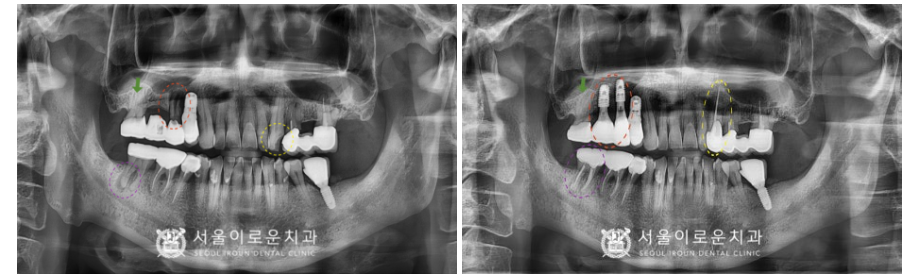

처음 내원 당시

환.자분의 파노라마 사진을 살펴보면

노란색 동그라미 표시의

위턱 왼쪽 송곳니(#23)이

충치로 인해 치아머리가 파절 되어 있어

신경치료 후 크라운 수복이 필요하였으며,

빨간색 동그라미 표시의

위턱 오른쪽 작은 어금니(#15)는

치아 뿌리가 파절되어 있어 발치 후

기존 상실된 첫 번째 큰 어금니(#16)와 함께

상악동 거상술을 동반하여

임플란트 식립이 필요하였습니다.

초록색 화살표의

위턱 오른쪽 두 번째 큰 어금니(#17)는

브릿지 제거 후 상태 평가 후

다시 크라운 수복 계획을

진행하기로 하였으며,

보라색 동그라미 표시의

아래턱 오른쪽 두 번째 큰 어금니(#47)는

타진 검사와 씹.는 검사에서

증.상이 있으며,

치아 뿌리 끝으로 병소가 관찰되어

신경치.료 후 크라운 치료가 필요했는데요.

임플란트 / 크라운 수복

신경치료 후 크라운 수복을

모두 마무리 한 모습입니다.

(2023.03.14ㅡ>2023.08.26)